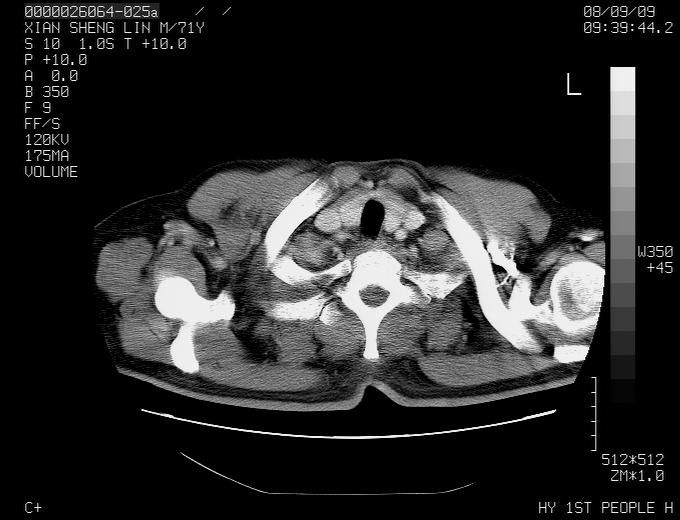

1.右肺血管源性病变;

2.肺癌

1,右肺中心型ca,气管隆突旁淋巴结转移。